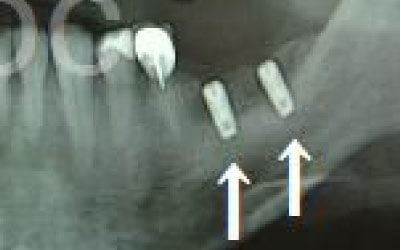

2 神経を傷つけるリスク

インプラントの手術では、顎の骨を通る神経を傷つけるリスクがあります。

しかし、事前にCTでしっかりと撮影し、三次元的に神経との距離を計測して治療計画を立てることで、心配は不要です。

また、当院では削りすぎを防ぐためのストッパーも使用しています。